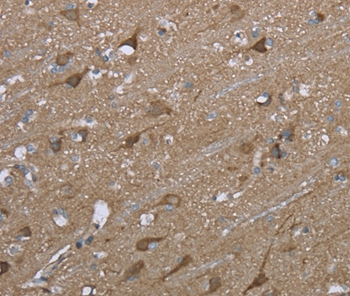

Immunohistochemical analysis of paraffin-embedded Human brain tissue using #36460 at dilution 1/50.